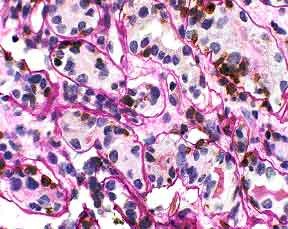

Figure 1. Tubulitis in the renal biopsy. Lymphocyte cytoplasm stains brown. Tubular borders are clearly delineated. UCHL-1/PASH 400x

The biopsy demonstrated moderate interstitial inflammation involving greater than 25% of the cortical area. The inflammatory infiltrate consisted predominantly of lymphocytes, with some admixture of plasma cells, eosinophils, and neutrophils. Several tubular profiles showed greater than four mononuclear cells per tubular cross-section. This was most clearly demonstrated on the PASH/T-cell stain (Figure 1). No tubular cross sections contained more than ten mononuclear cells. The PASH/T-cell stain confirmed that the majority of lymphocytes present were T-cells. A diagnosis of acute cellular rejection, tubulointerstitial type was made (Banff 1997 acute rejection, type IA).

The key element in making a diagnosis of acute cellular rejection, tubulointerstitial type, is the identification of tubulitis. This can be challenging because lymphocytes in foci of presumptive tubulitis can be difficult to distinguish from tubular nuclei on standard stains like H&E or PASH (Figure 2). Immunohistochemical stains for LCA or T-cell markers can reliably identify the lymphocytes, but it may be difficult for these stains to distinguish whether the lymphocytes are truly inside the tubular basement membrane or merely adjacent to the tubule (Figure 3). Combining a basement membrane stain (PAS) with a T cell stain (UCHL-1) elegantly solves the problem of both specifically identifying T-lymphocytes and precisely determining their location (Figure 4). Thus, the presence of tubulitis can quickly and accurately be confirmed or excluded. This combination of UCHL-1/PASH greatly improves the accuracy of diagnosing of acute cellular tubulointerstitial rejection and helps determine the therapeutic course and prognosis.